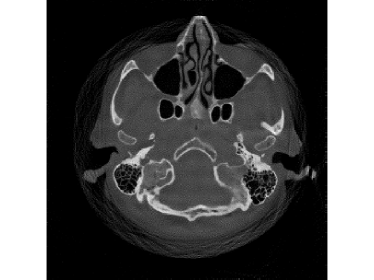

When the detectable range is smaller such that κ=0.4pmax𝜅0.4subscript𝑝\kappa=0.4p_{\max}, saturation becomes worse. Then the performance of FBP and SART, even with water cylinder extrapolation and the ISD scheme, dramatically drops. In practice, this heavy saturation rarely happens and is out of the scope of FBP-WCE. But even with this heavy saturation, the proposed M1bit-CSR-ISD can output a good result. The reconstructed images and enlargements of a region are illustrated in Fig.12 and Fig.13, respectively. In this case, both FBP-WCE and SART-ISD fail to restore the clear outer boundaries of the patient, while M1bit-CSR-ISD is still able to achieve this in a more accurate manner. We further report the saturation detection result in Fig.14, from which one can observe that most of the saturations have been properly detected.

Refer to caption

Figure 13: An enlargement of a region of the clinical data, which is marked by yellow rectangle in Fig.12: (a) ground truth; (b) FBP-WCE; (c) SART-ISD; (d) M1bit-CSR-ISD.